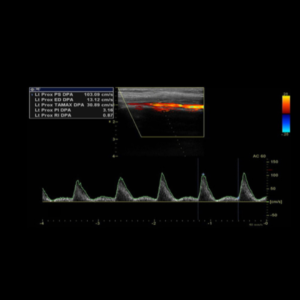

Ecografía Doppler Arterial

La ecografía Doppler arterial es un estudio de ecografías que estudia las diferentes ramas arterias de miembro superior o inferior, evaluando su calibre y descartando la presencia de placas ateromatosas o estrechez que indiquen un flujo lento, por lo tanto descarta insuficiencia arterial.